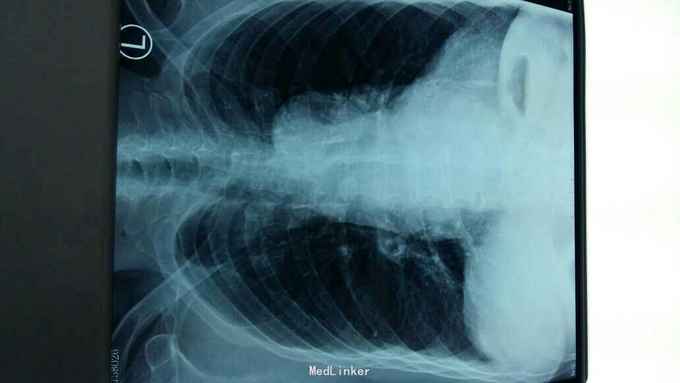

摔伤后胸痛、胸闷1天 1天前在自家劳动时摔伤胸部,伤后胸痛、胸闷,呼吸急促,活动后加重,不敢平卧,为诊治来院。

右侧胸部第4肋及第5胸肋关节处可触及骨摖感,触痛阳性。右肺呼吸音减弱。

1、右侧第4肋骨骨折;2、右侧第5胸肋关节脱位。 1、局部胸带外固定;2、促进骨愈合药物;3、平喘、化痰、预防感染;4、密切观察病情变化,随时复查。